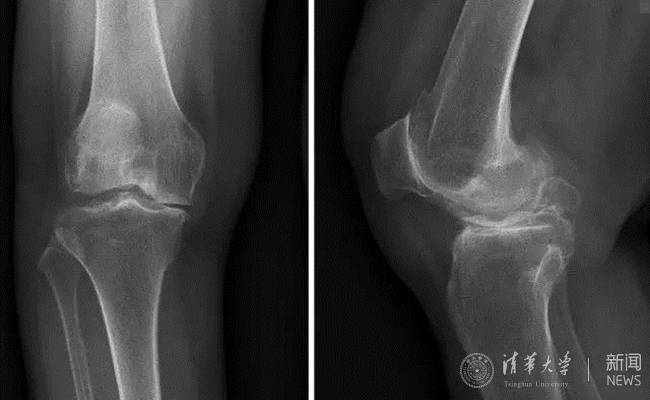

患者术前膝关节正侧位平片。